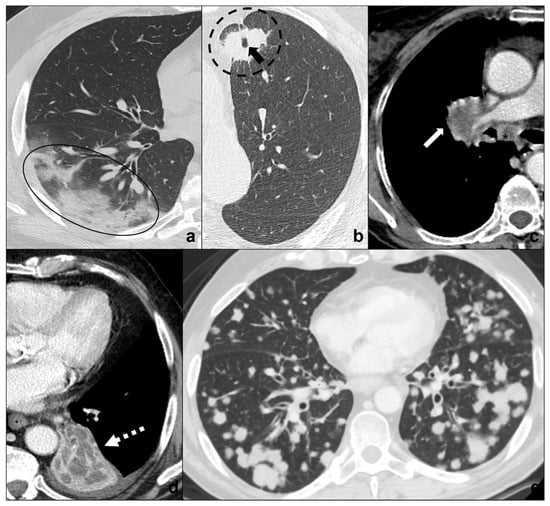

- tumors are generally focal entities and appear as ground-glass opacities (atypical adenomatous hyperplasia likely being ≤5 mm, adenocarcinoma in situ generally being bigger, even measuring ≤3 cm), or ground-glass opacity surrounding a nodule (≤5 mm in minimally invasive adenocarcinoma and >5 mm in lepidic predominant adenocarcinoma);

- even if tumors are multicentric, such as invasive mucinous adenocarcinoma, they tend to grow even after antibiotic or anti-inflammatory treatment;

- additional findings such as cysts (cystadenocarcinoma);

- cleavage invasion;

- lymphangitic carcinomatosis (Figure 3b);

- mediastinal lymphadenopathies (Figure 4e) and pleural effusions.